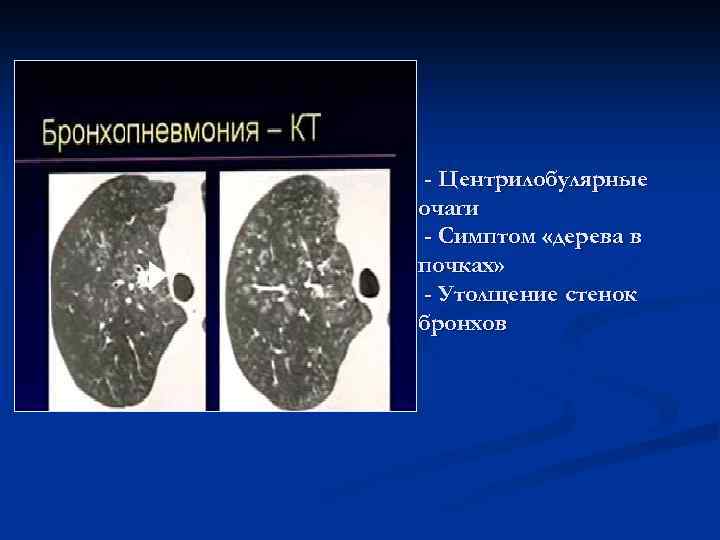

- Центрилобулярные очаги - Симптом «дерева в почках» - Утолщение стенок бронхов

Бронхопневмония Локальный характер изменений (1 -2 сегмента) Перибронхиальные, центрилобулярные очаги или небольшие инфильтраты Субплевральное расположение очагов Контуры очагов достаточно четкие Денситометрическая плотность - +20…+40 HU Просвет бронхов свободен, стенки утолщены, в процесс вовлечены бронхи 5 -7 порядка